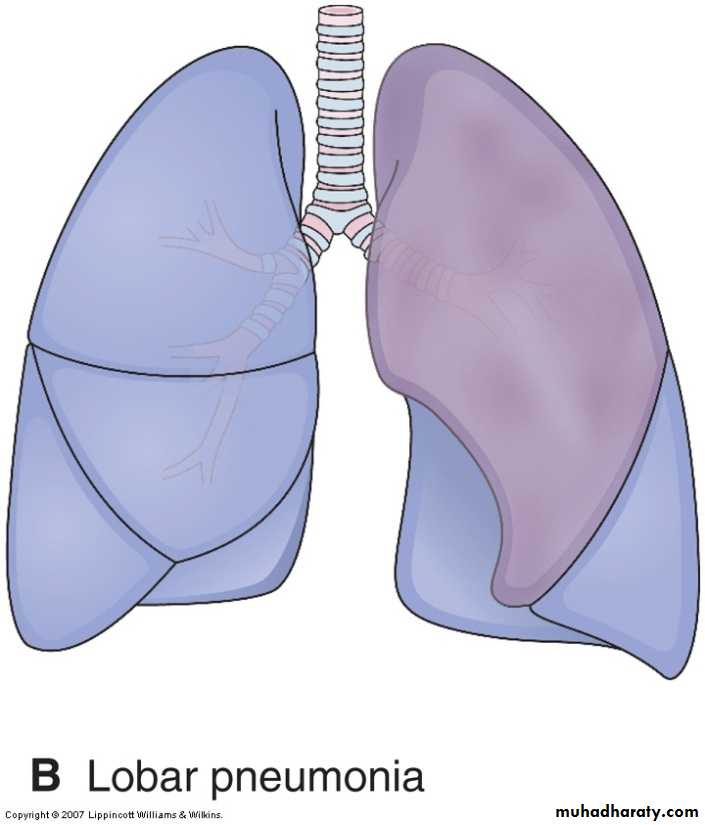

2-lobar pneumonia the contiguous airspaces of part or all of a lobe are homogeneously filled with an exudate that can be visualized on radiographs as a lobar or segmental consolidation Streptococcus pneumoniae is responsible for more than 90% of lobar pneumonias.

Lobar pneumonia—gray hepatization, gross photograph. The lower lobe is uniformly consolidated.

In the, gray hepatization, the lung is dry, gray, and firm, because the red cells are lysed, while the fibrinosuppurative exudate persists within the alveoli